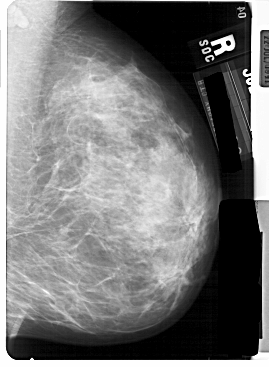

A_1757_1.RIGHT_CC

RIGHT_CC LINES 5491 PIXELS_PER_LINE 3751 BITS_PER_PIXEL 12 RESOLUTION 43.5 NON_OVERLAY